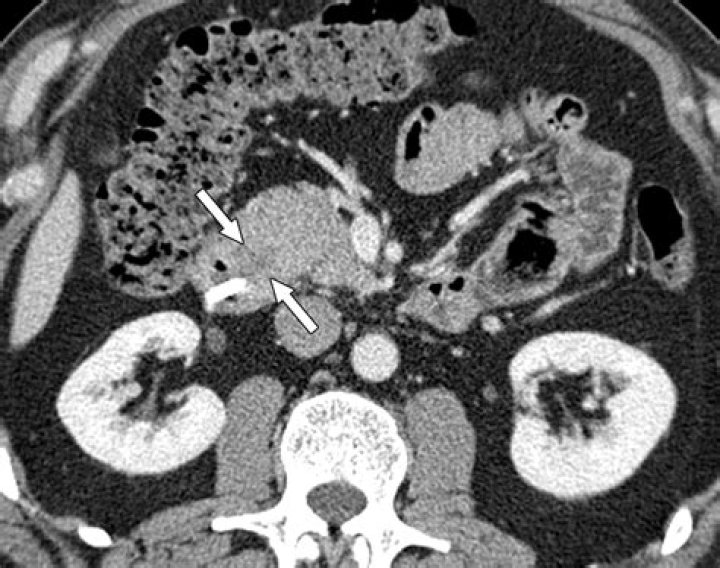

Does CT scan show autoimmune pancreatitis?

A relatively specific main pancreatic duct change of AIP is multifocal narrowing, and this may be depicted on CT or MRCP (1, 19).

What does chronic pancreatitis look like on CT?

CT features of chronic pancreatitis that can be visualized on CT scans include dilatation of the main pancreatic duct; calcifications; changes in size, shape, and contour; pseudocysts; and bile duct changes. (See the CT images of chronic pancreatitis below.)